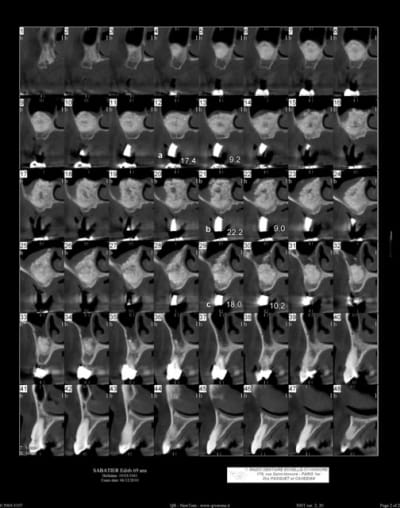

patiente ayant été implantée il y a 12 jours et toujours mal

le sinus lift a été pratiqué il y a 8 mois

Aspect lacunaire du biomat au scanner = sucre mouillé infecté...car non vivant et non vascularisé

Toujours est il qu'avec un agrandissement on verrait sûrement plein de petites lacunes , mais déjà là les grosses...

je lui ai donné un traitement pour une sinusite (augmentin, solupred, lavage des fosses nasales), et precription d'un cone beam dans 10 jours

le sinus a été greffé il y a environ 8 mois

et les implants ont été posés il y a 15 jours